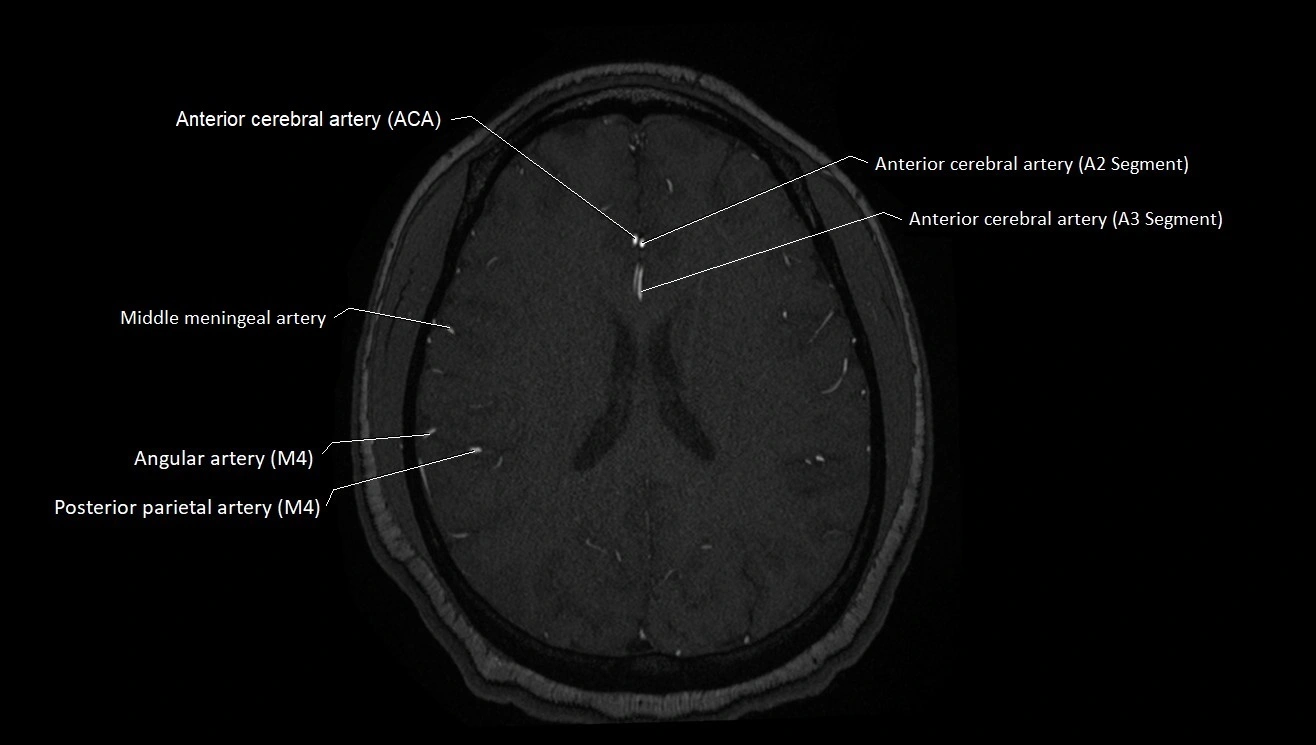

MRA (Magnetic Resonance Angiography):

• Flow-related enhancement makes the AChA appear as a bright, linear vascular signal against suppressed background

• High sensitivity for origin and proximal course; distal branches may be too small to resolve

• Detects stenosis, occlusion, aneurysm, AVM feeders